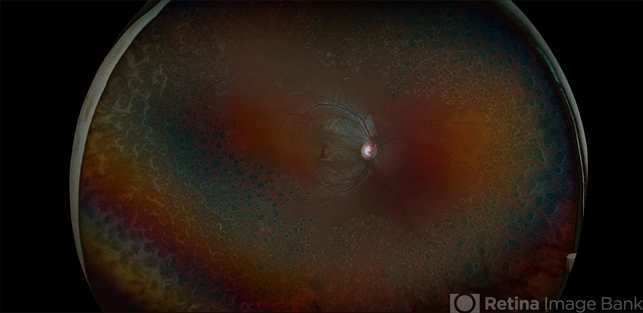

- Systemic Lupus Erythematosus (SLE) Vasculitis, occlusive vasculitis, pan-retinal photocoagulation (PRP), NVE, NVD

- Fundus photographs of an 13-year-old boy with Systemic Lupus Erythematosus (SLE) Vasculitis in both eyes s/p PRP laser. Patient is doing well s/p PRP Laser OU and with continued use of oral medications. Patient will be monitored with follow up exams to check for recurring vasculitis or recurring/worsening NVE/NVD. Patient is to continue ongoing management with Rheumatologist.